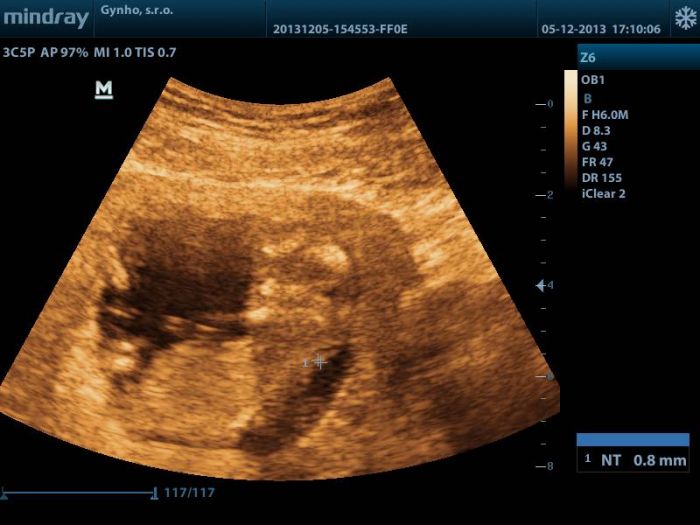

Ahojte holky, tak dneska jsem byla na kontrole u sveho Dr, delal mi utz pres bricho, takze obrazek nic moc, ale i tam prikladam